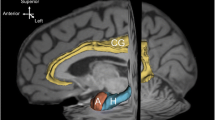

The MPRAGE was skull stripped by means of FSL bet toolbox and the brain tissues were segmented, using the Sienax algorithm [27], in gray matter (GM), WM and cerebrospinal fluid (CSF).

pCASL (pseudo-continuous arterial spin labeling) dataset

The tag and control images were preprocessed performing the standard procedures of averaging, realignment and motion correction, using ANT’s software package. Then, the estimation of CBF maps was performed using Oxford_asl followed by their calibration by means of asl calib tools [28]; the required parameters were set as follows: T1 of blood tissue = 1.2 s, T1 of blood = 1.36 s, tagging efficiency = 0.8 accordingly to [29]. Finally, a partial volume correction was performed, and successively the CBF maps were nonlinearly registered, using ANTS, to the MNI standard space, using GM and WM masks derived from the MPRAGE. For each subject, the average perfusion, measured by CBF as ml/100 g/min, was extracted from a total of 62 cortical and subcortical parcels per hemisphere accordingly to the Harvard–Oxford atlas (http://www.cma.mgh.harvard.edu/fsl_atlas.html; http://fsl.fmrib.ox.ac.uk/fsl/fslwiki/Atlases).